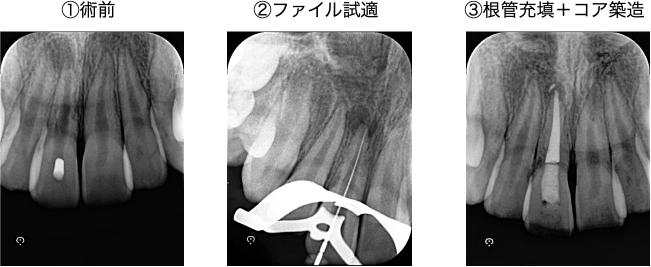

ラバーダムを装着し、機械を使用して歯の根の長さを測定します。さらに、レントゲン写真を撮影し、長さのエラーがないかをチェックします。ここで大きなエラーがあると、治療の失敗につながってしまうため、慎重に器具操作を行います。

根の先端部分が大きく開いていたため、MTAセメントで根尖部を封鎖し、治療は完了となりました。

| 根管洗浄 | 次亜塩素酸ナトリウム溶液・EDTA溶液 |

| 根管貼薬 | なし(1回で治療を終えたため) |

| 拡大号数 | 50/04 |

| 根管充填 | MTAセメント |